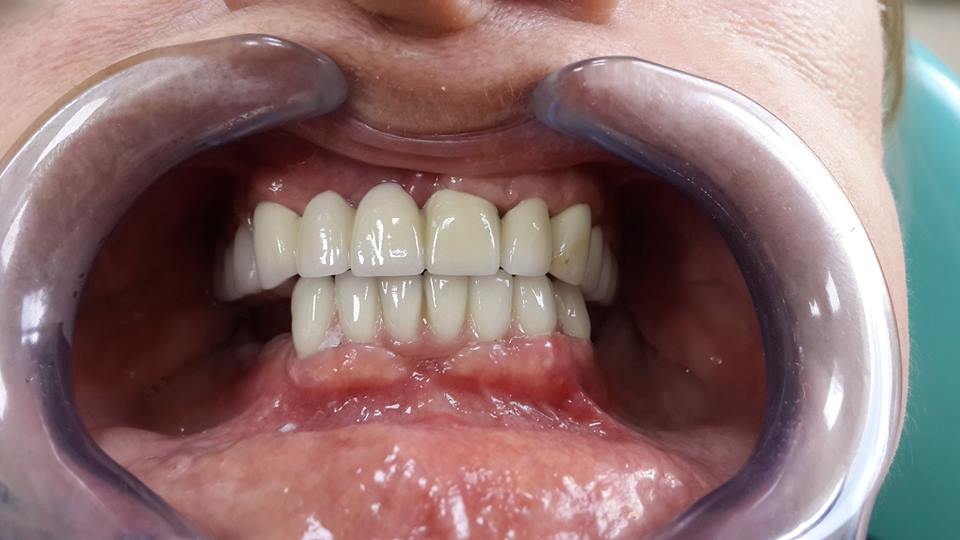

An example of complete rehabilitation of the oral cavity. Treatment included the removal of the old prosthesis, treatment of paradontitis, removal of a large cyst, implantation, clasp prosthesis.